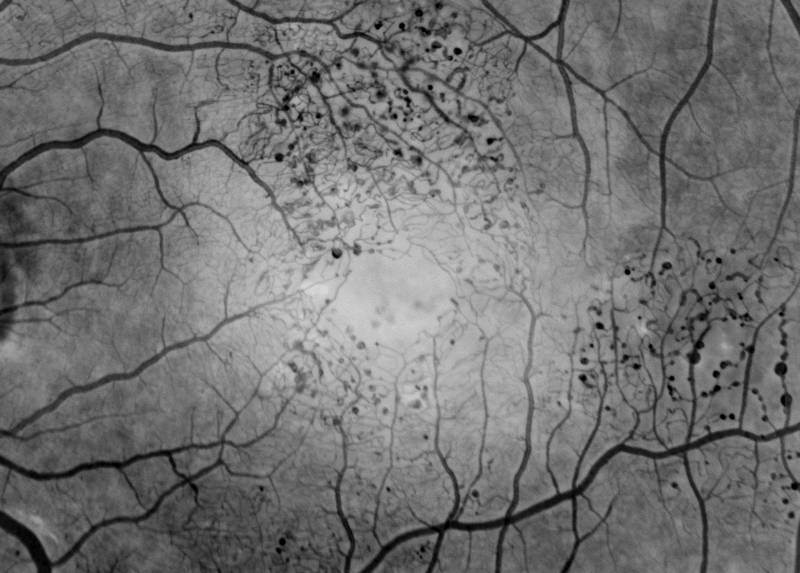

Introduction of Indocyanine-Green Angiography

Introduction of ICG angiography was a major accomplishment, which was possible only through the assimilation of digital imaging and the use of a fluorescent green dye of longer wavelength to image the choroidal circulation.

Guyer D, Yannuzzi L, Slakter J, Sorenson J, Orlock D.

The Status of Indocyanine-green videoangiography. Current Opinion in Ophthalmology 4:III;3-6, 1993.

Detection of Occult CNV using Indocyanine-Green Angiography

Digital Idocyanine-green Videoangiography of Occult Choroidal Neovascularization

Guyer D, Yannuzzi L, Slakter J, Sorenson J, Hope-Ross M, Orlock D

Ophthalmol 101(10): 1727-1737, 1994